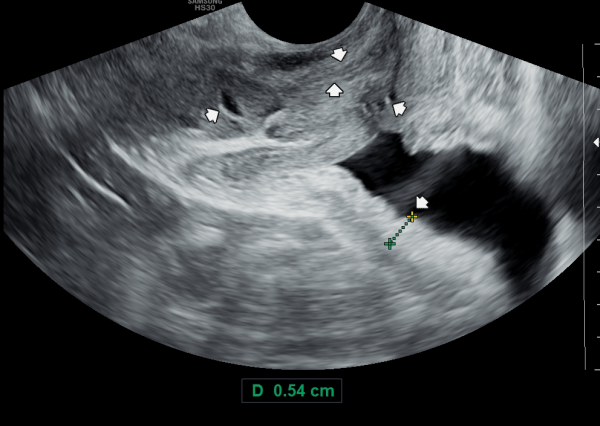

서울가정의학과의원에 첫 내원 당일 지난 5개월동안 회음부 통증과 배뇨장애로 타 비뇨기과 여러곳에서 치료를 했으나 증상의 호전이 없다고 내원 당일 검사한 경직장 전립선 초음파 검사상 사정관 입구의 석회화와 사정관의 섬유화 그리고 정낭의 낭종이 관찰되는 초음파 자료입니다.

On the first visit to Seoul Family Medicine Clinic, the patient reported having perineal pain and urination problems for the past five months, despite receiving treatment at several other urology clinics with no improvement.

A transrectal prostate ultrasound performed on the day of the visit showed calcification at the opening of the ejaculatory duct, fibrosis (scarring) of the duct itself, and cysts in the seminal vesicles.

내원 당일 경직장 전립선 초음파 검사상 오랜 세월동안 사정관의 벽이 수명을 다한 거짓 중층 원주 상피 세포가 탈락되어 사정관 입구에 막혀 두텁게 쌓여 있고 요도에도 탈락된 상피 세포가 쌓여서 정낭과 정관 그리고 전립선액 과 배뇨등의 순환 장애를 보이고 있는 경직장 전립선 초음파 사진입니다.

This transrectal prostate ultrasound image, taken on your first visit, shows that over many years, the wall of the ejaculatory duct has been blocked by a buildup of old, shed pseudostratified columnar epithelial cells. These cells have accumulated at the opening of the ejaculatory duct and in the urethra, leading to circulation problems in the seminal vesicles, vas deferens, and prostate fluid, as well as urinary flow issues.